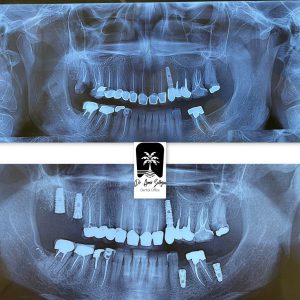

ایمپلنت فرش ساکت چیست؟

ایمپلنت فرش ساکت یعنی همان زمان که دندان را خارج می کنیم ، همان لحظه ایمپلنت را قرار می دهیم.